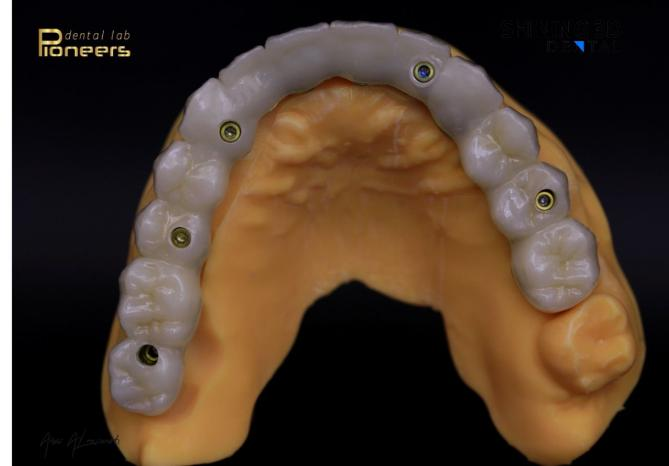

After the patient had adapted to the provisional restorations, with healthy gingival recovery and successful osseointegration, the final prosthesis was fabricated using a milling machine. The try-in was first performed extraorally on a physical model to confirm passive fit, evaluate occlusion, and assess tooth morphology.

Fig. 27–32: Final prosthesis